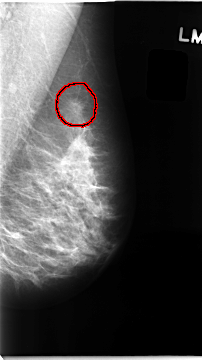

C_0097_1.RIGHT_CC

RIGHT_CC LINES 4736 PIXELS_PER_LINE 2608 BITS_PER_PIXEL 12 RESOLUTION 50 NON_OVERLAY

FILE: C_0097_1.LEFT_CC.OVERLAY

TOTAL_ABNORMALITIES 1

ABNORMALITY 1

LESION_TYPE MASS SHAPE IRREGULAR MARGINS SPICULATED

ASSESSMENT 5

SUBTLETY 5

PATHOLOGY MALIGNANT

TOTAL_OUTLINES 1

BOUNDARY